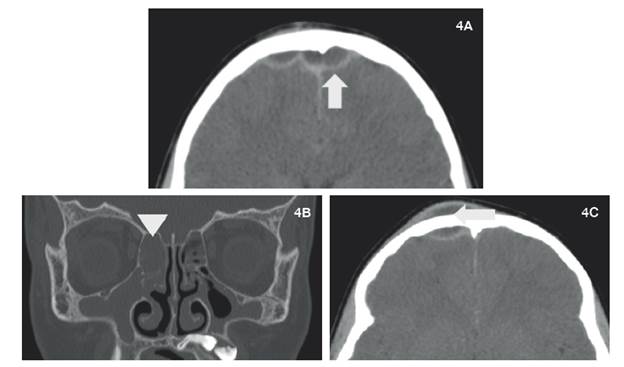

Escanografía de senos paranasales en cortes axiales y reconstrucción coronal, donde se aprecia colección de tipo epidural frontal (4A, flecha), vinculado con material con densidad de tejidos blandos etmoidomaxilar bilateral (4B, punta de flecha) y colección liquida prefrontal (4C, flecha).

Figura 4: Escanografía de senos paranasales en cortes axiales y reconstrucción coronal, donde se aprecia colección de tipo epidural frontal (4A, flecha), vinculado con material con densidad de tejidos blandos etmoidomaxilar bilateral (4B, punta de flecha) y colección liquida prefrontal (4C, flecha).